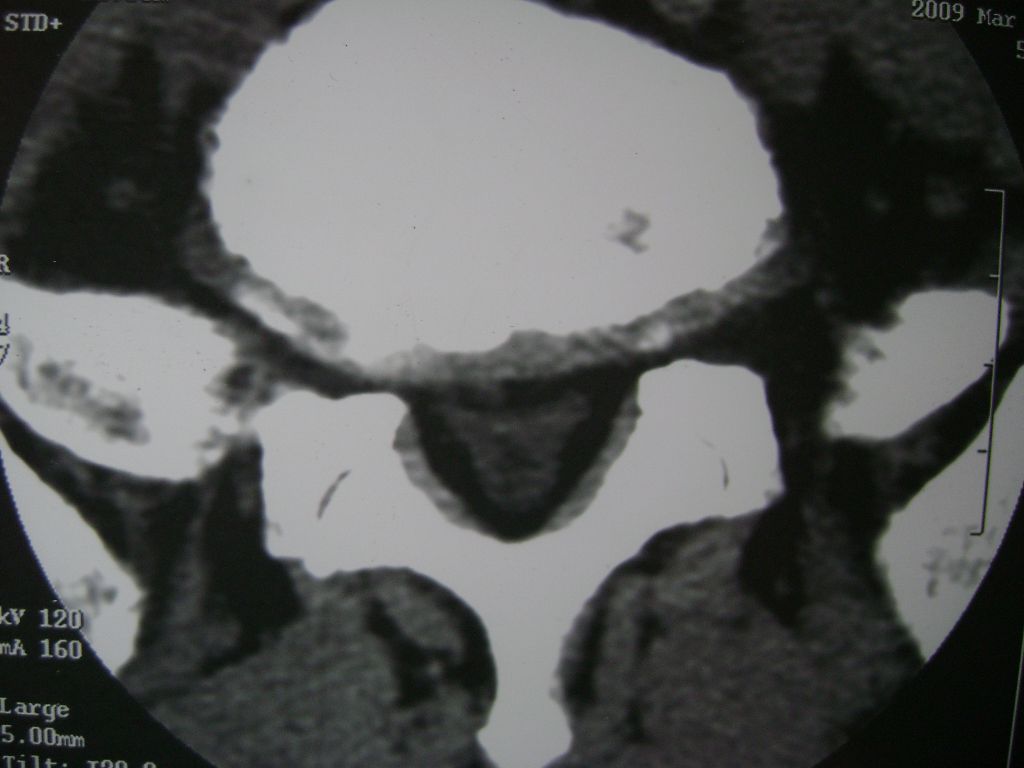

m  50  腰痛

两个椎盘均有膨出及突出改变,下一个尚有椎盘积气,后纵韧带钙化,另椎管脂肪过多症

椎间盘膨出,后纵韧带钙化,骨质增生

两个椎间盘中央型重度突出,黄韧带增厚。

两个椎间盘膨出并突出,下一个椎间盘变性;双侧黄韧带钙化。